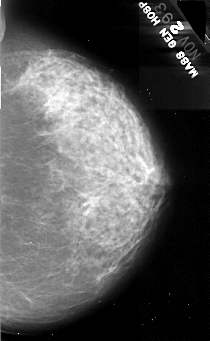

A_1078_1.RIGHT_MLO

RIGHT_MLO LINES 5491 PIXELS_PER_LINE 3406 BITS_PER_PIXEL 16 RESOLUTION 42 NON_OVERLAY